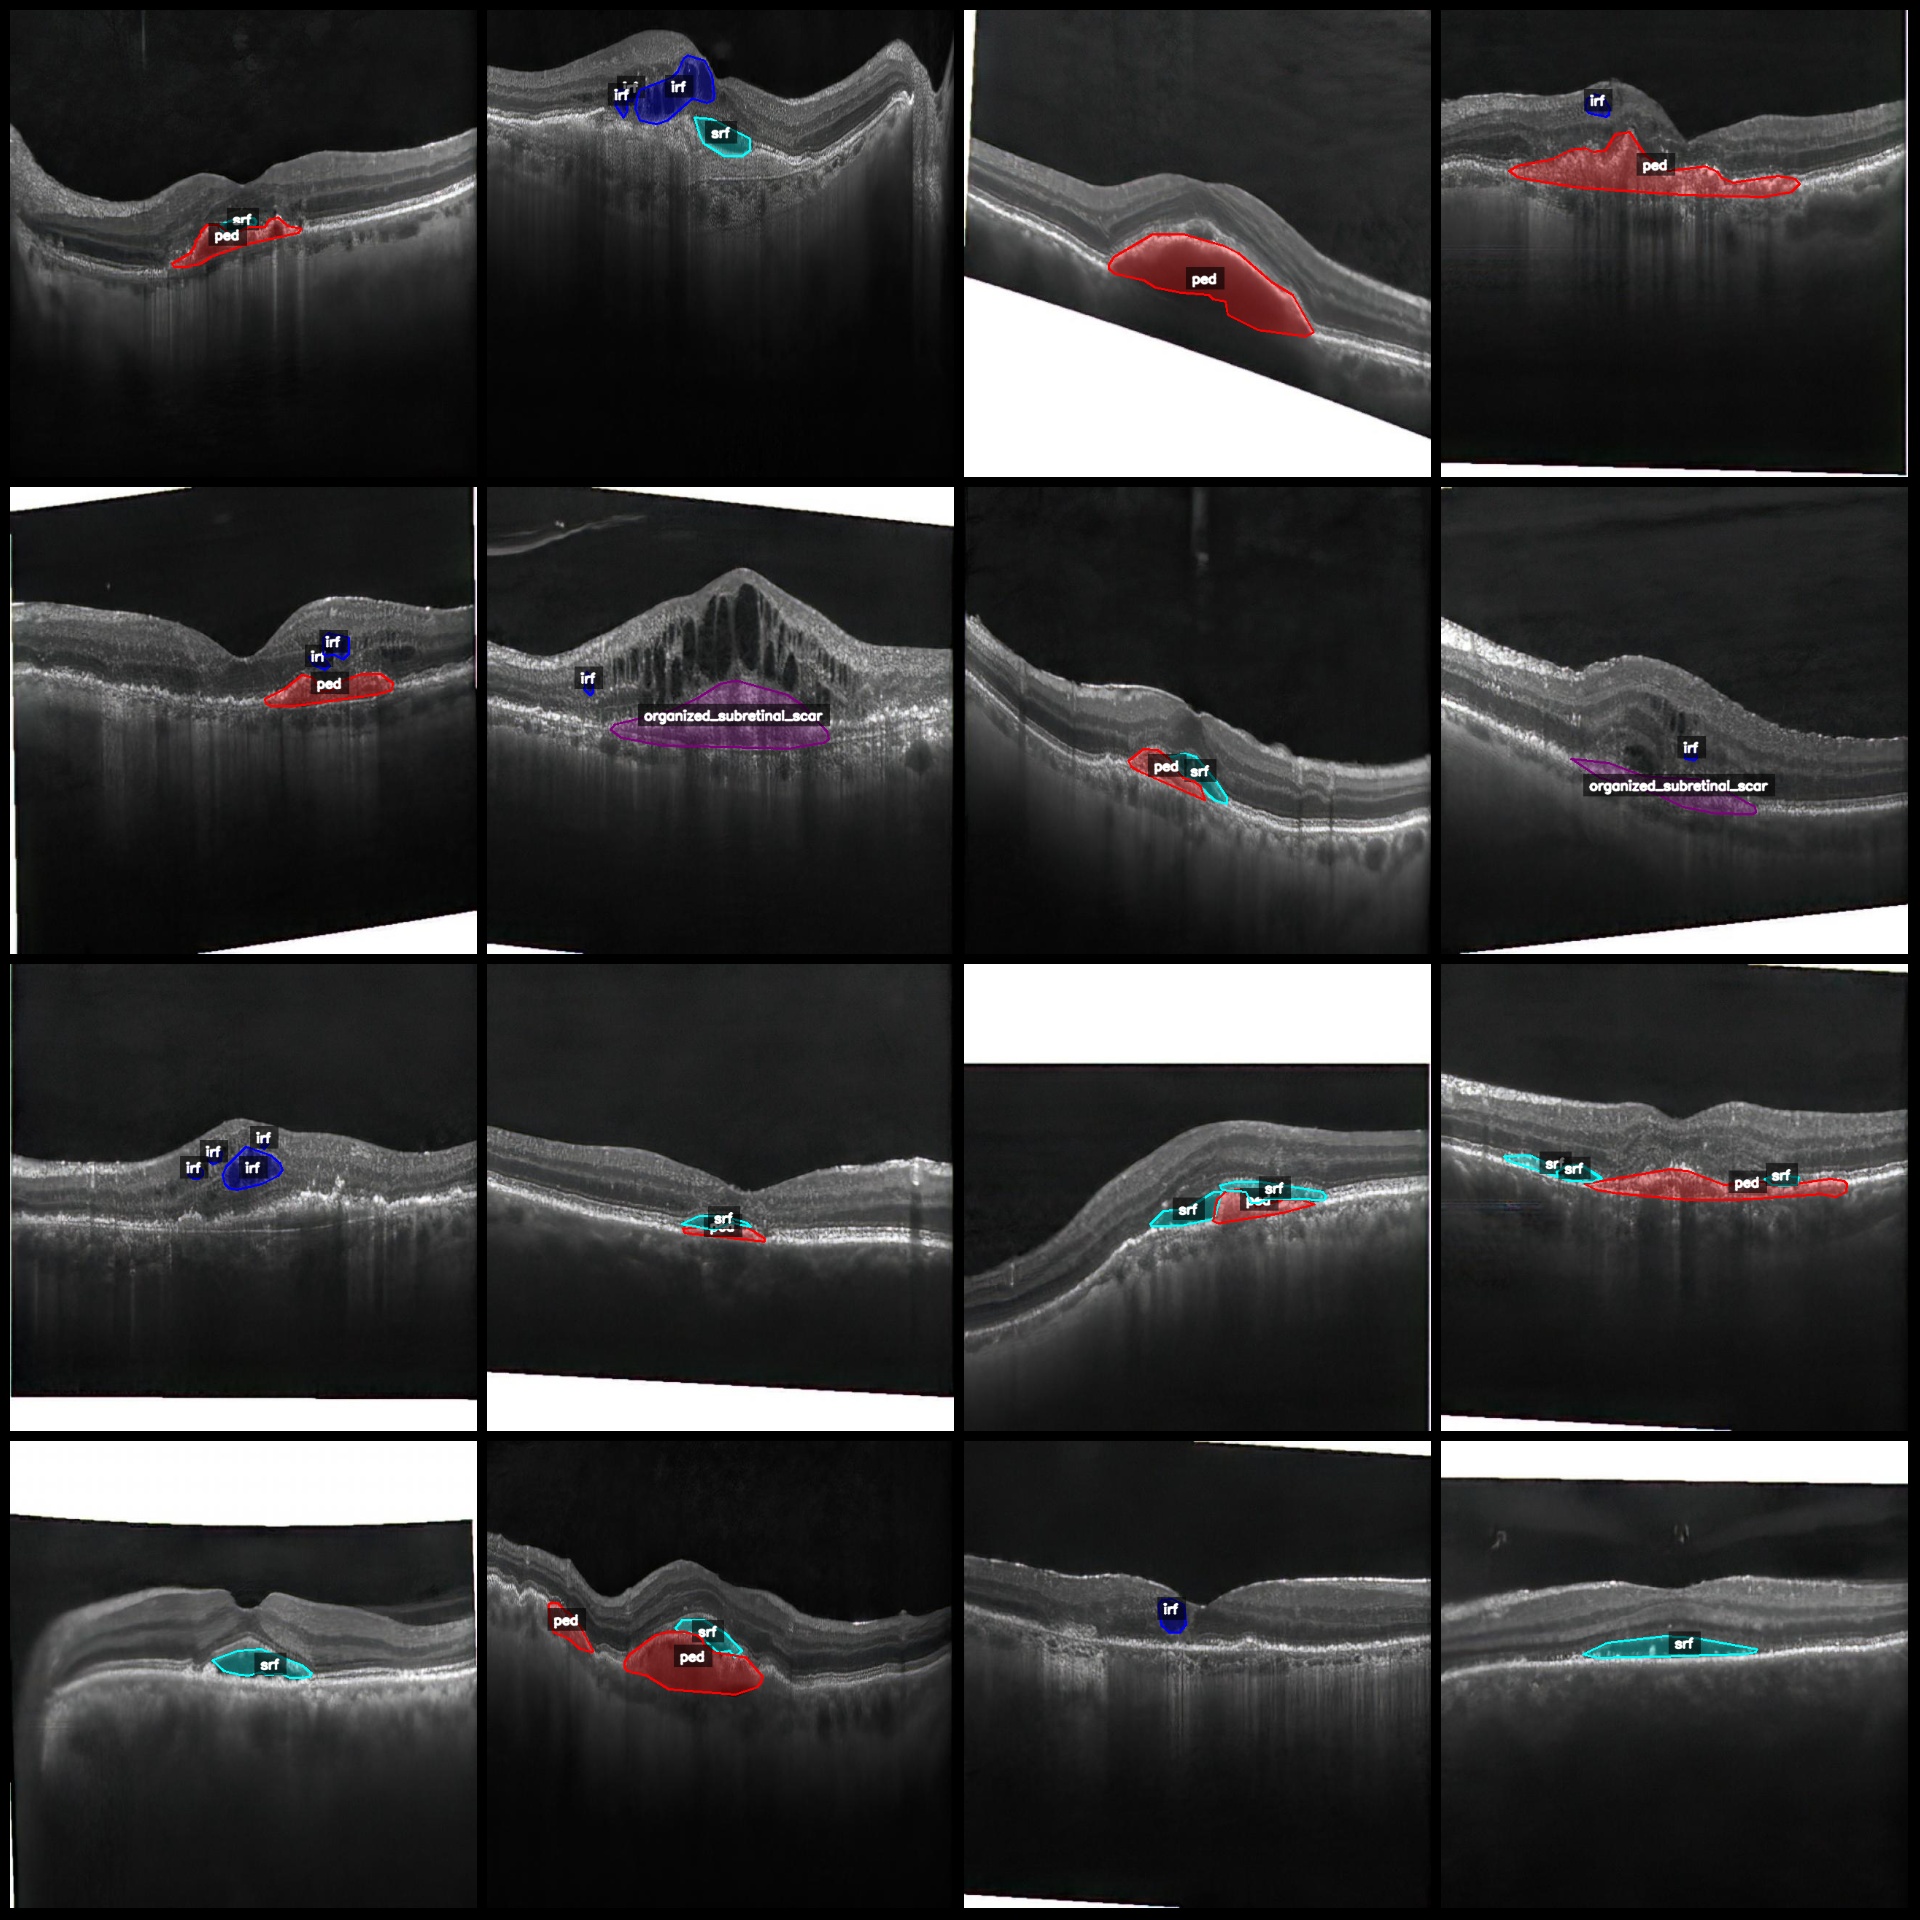

标注类别名称:["irf","organized_subretinal_scar","ped","srf","subretinal_hyperreflective_material","virteliform_lesion"]

每个类别标注的框数:

irf(视网膜内高反射点) count = 4878

organized_subretinal_scar(组织化视网膜下瘢痕) count = 326

ped(色素上皮脱离) count = 3611

srf(视网膜下液) count = 3794

subretinal_hyperreflective_material(视网膜下高反射物质) count = 91

virteliform_lesion(玻璃膜疣样病变) count = 194

总框数:12894

标注规则:对类别进行画多边形框polygon

标注例子:

标注绘制结果: